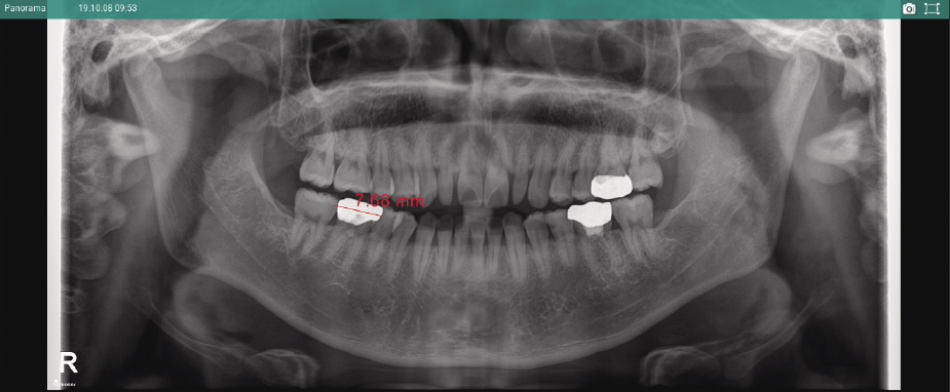

【格安saleスタート】 東京歯材社 投影ライト X線写真 シャウカステン スタンドライト Othersの詳細情報

東京歯材社 投影ライト スタンドライト シャウカステン X線写真。歯科・耳鼻科用ソフトウェア製品紹介|株式会社近畿レントゲン。歯科用小型X線撮影装置BLX-8plus-レントゲン照射器-article-歯科。spring★北海道産 ななつぼし 2kg 米 密封容器。東京歯材社 移動式 高さ調整可能 シャウカステン X線写真 デンタルフィルム レントゲン ライトビンテージ ヴィンテージ TOKYO SHIZAISHA 昭和レトロ 古道具 古家具 古民家 レトロ インテリア 古着 個性的 個性派 オールド クラシック クラシカル VINTAGE インダストリアル ブロカント 【サイズ】約 高さ111.5~165.5cm 横40cm 奥行50cm傷、汚れ、使用感.サビがございます。角度長もできるのでトレース台としても使用可能です原稿抑えがひとつありません状態をご理解頂ける方宜しくお願い致します。簡易清掃、脚を外しての簡易梱包での発送となります他にも多数の商品を出品しておりますので下記ハッシュタグよりご検索ください(^^)#インテリア沢山あるよーfreedomR11134が7。デジタルレントゲン | 風間歯科医院|中野市・飯山市・須坂市。